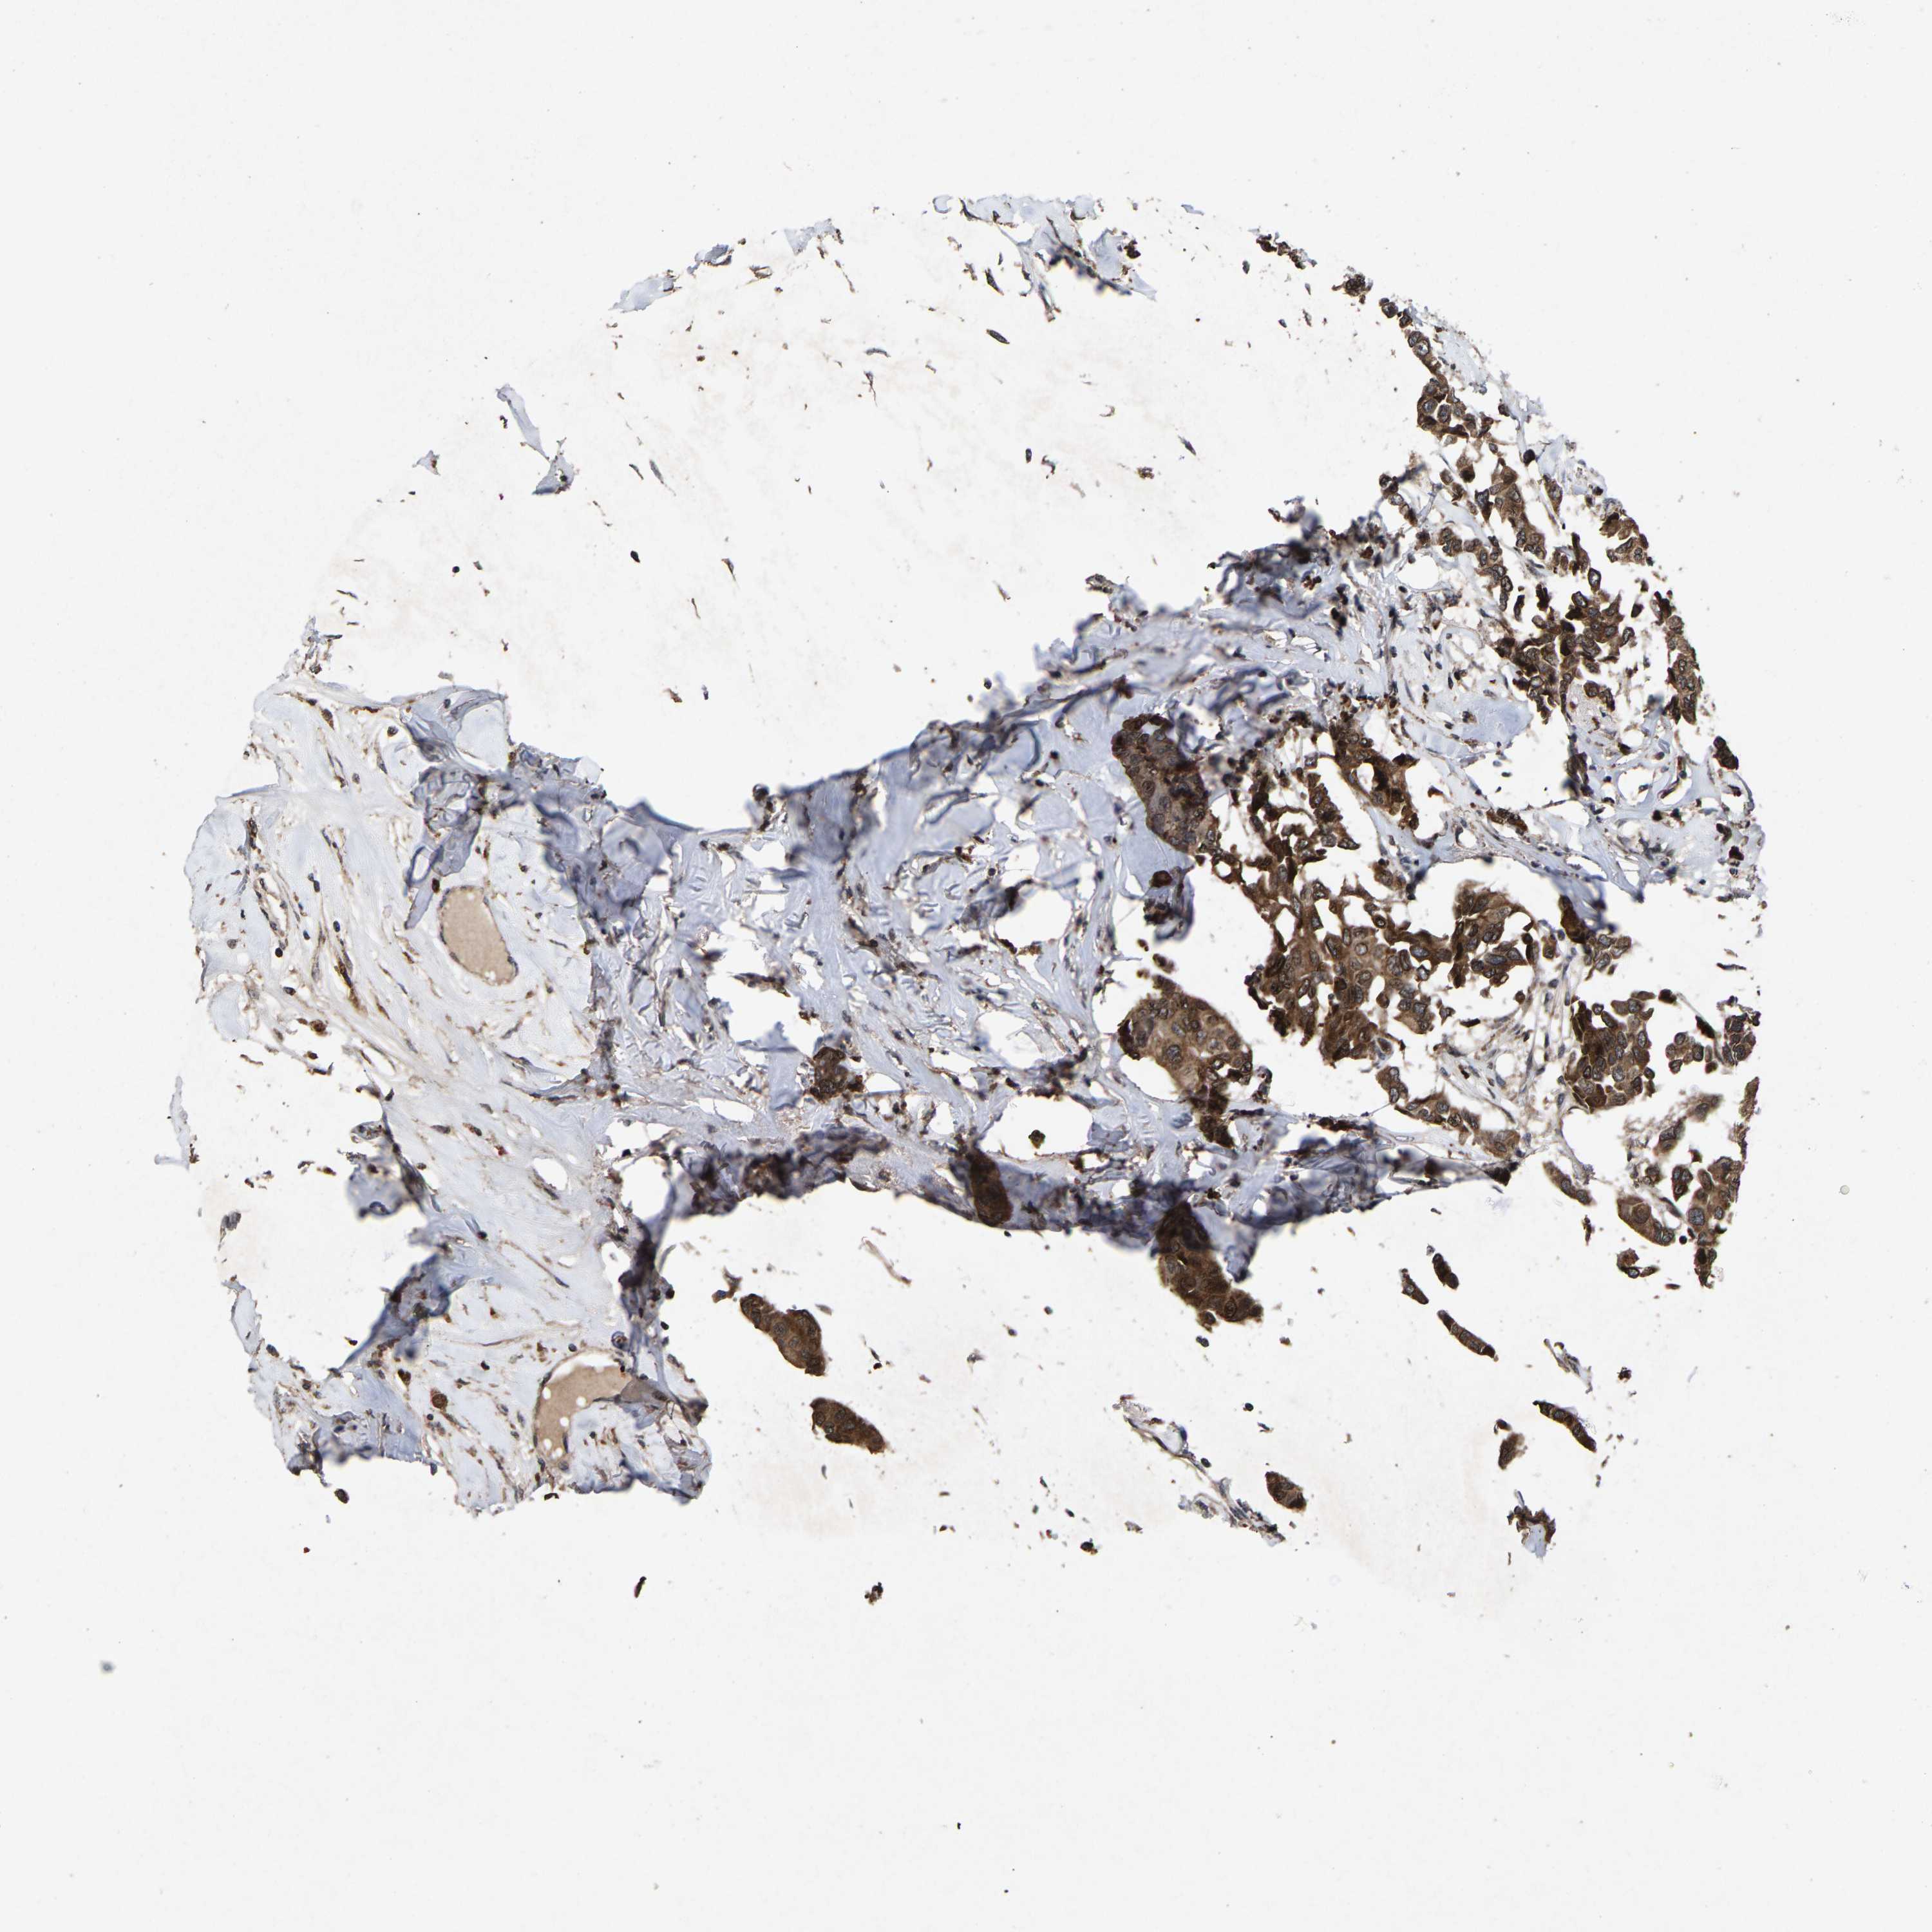

CANCER BREAST CANCER Show tissue menu

BRCA TCGA BRCA VALIDATION PROTEIN EXPRESSION